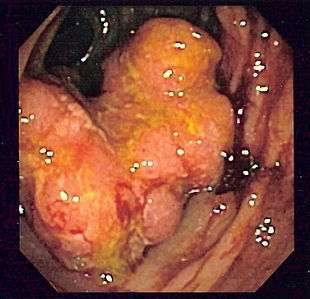

Endoscopic image of colon cancer identified in sigmoid colon on screening colonoscopy in the setting of Crohn's disease

Cancers on the right side of the large intestine (ascending colon and cecum) tend to be exophytic, that is, the tumor grows outwards from one location in the bowel wall. This very rarely causes obstruction of feces, and presents with symptoms such as anemia. Left-sided tumors tend to be circumferential, and can obstruct the bowel lumen, much like a napkin ring, and results in thinner caliber stools.